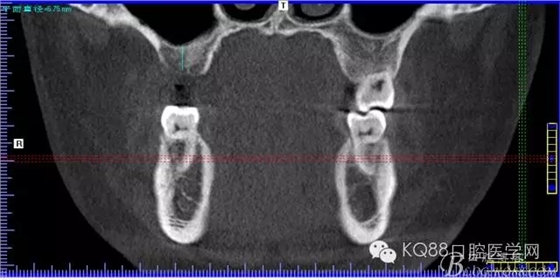

下面是拔牙后三個(gè)月的CBCT。垂直骨高度約6.7mm。

另外一個(gè)切面。垂直骨高度不夠,準(zhǔn)備 :做內(nèi)提升,植骨,植入植體。